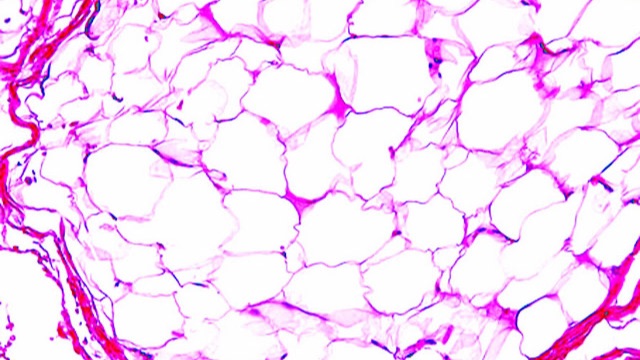

Составная лекция для студентов 3 курса медицинских ВУЗов по онкоморфологии: 00:00 - мезенхимальные опухоли 00:48:38 - меланоцитарные опухоли 01:20:48 - опухоли нервной системы и оболочек мозга 01:37:07 - герминоклеточные опухоли,